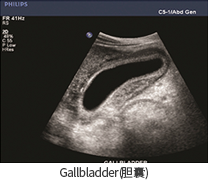

• Gallbladder(담낭)